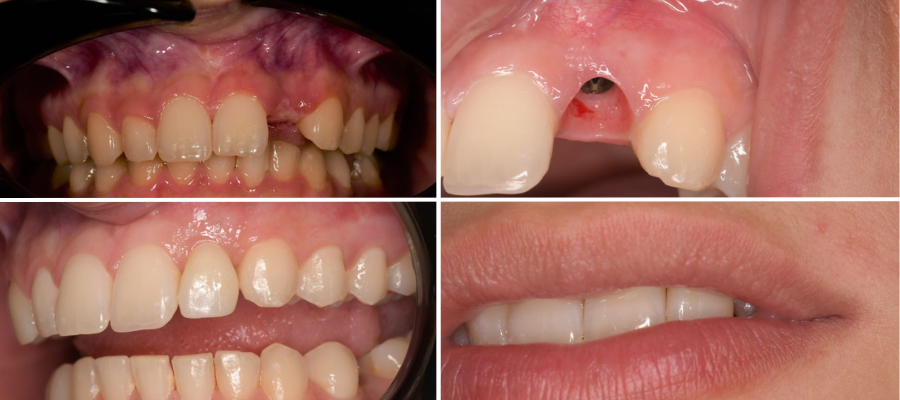

Regeneracija kosti i mekog tkiva

Gingivalne recesije u narodu poznatije kao „povlačenje zubnog mesa" moguće je korigirati kirurškim zahvatom te vratiti gingivu (zubno meso) u fiziološki položaj mikrokirurškim tehnikama. Zahvati koje odrađujemo kod regeneracije kosti i mekog tkiva su podizanje dna sinusa (sinus lift) i nadomještanje izgubljenog volumena kosti (augmentacija kosti, regeneracija kosti).

Implantologija - ugradnja dentalnih implantata

Dentalna implantologija je grana dentalne medicine koja objedinjuje znanje iz kirurgije, parodontologije i protetike i bavi se ugradnjom implantata u bezubu kost gornje ili donje čeljusti.

Marković Dental Clinic koristi najstariji, najistraživaniji i najkvalitetniji sustav dentalnih implantata Švedskog proizvođača Nobel Biocare.